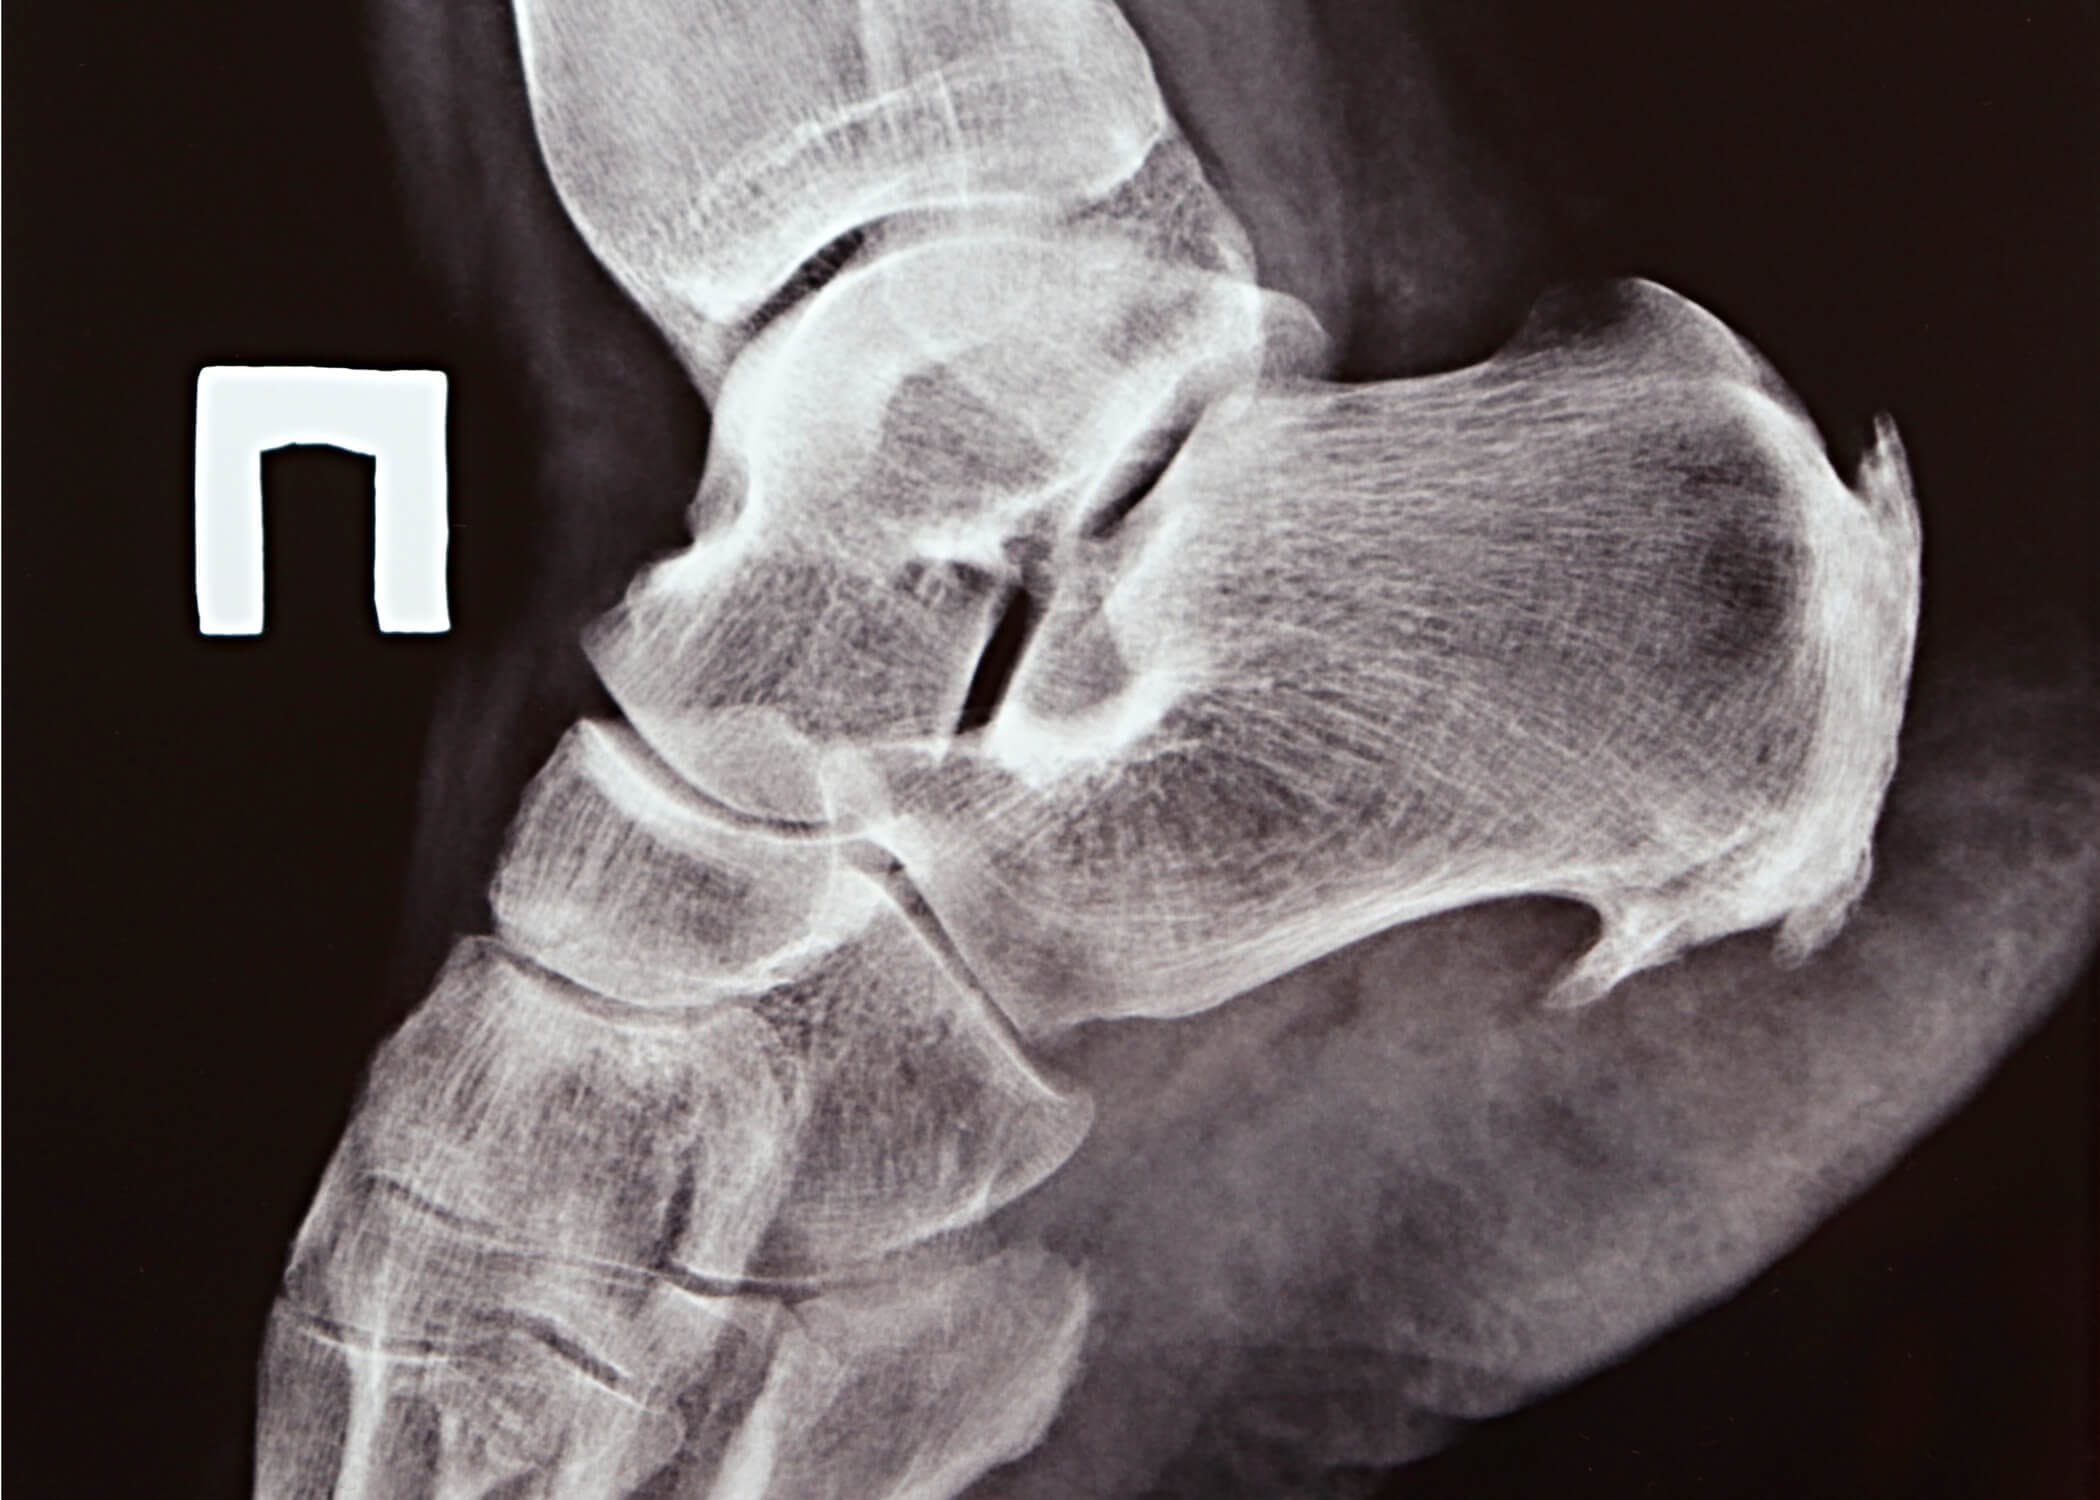

HaglundX ray 1

Haglund hastalığının tanısı, hastanın fizik muayenesi sırasında konur ve ele gelen kemik deformitesinin belirgenliği ilk bulgudur. Ancak hastalarda çekilen röntgen ve ileri tetkik yöntemleri ile kemiğin büyüklüğü ve çevre dokulara verdiği zarar hakkında net bilgi elde edilir.